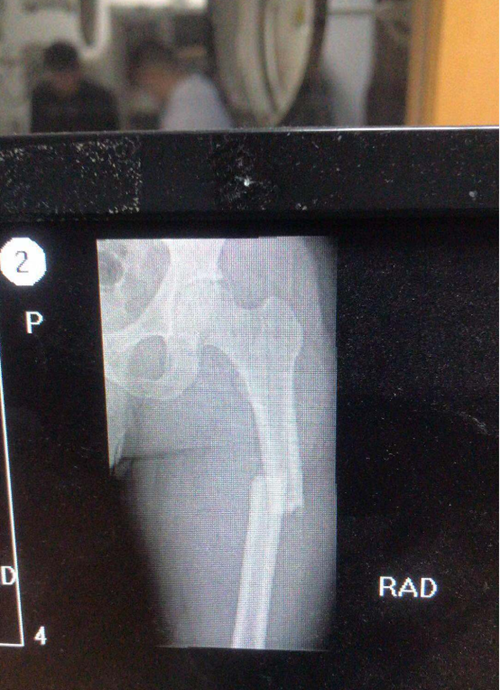

抓捕结束,王泽奇才感到左腿一阵剧痛。同事们连忙将他紧急送往医院。经过X光片检查,大家都被惊呆了:左腿股骨近端骨折并错位。难以想象他是凭着怎样的毅力,坚持完成了抓捕任务。

X光诊断结果显示:王泽奇左腿股骨近端骨折并错位 警方供图